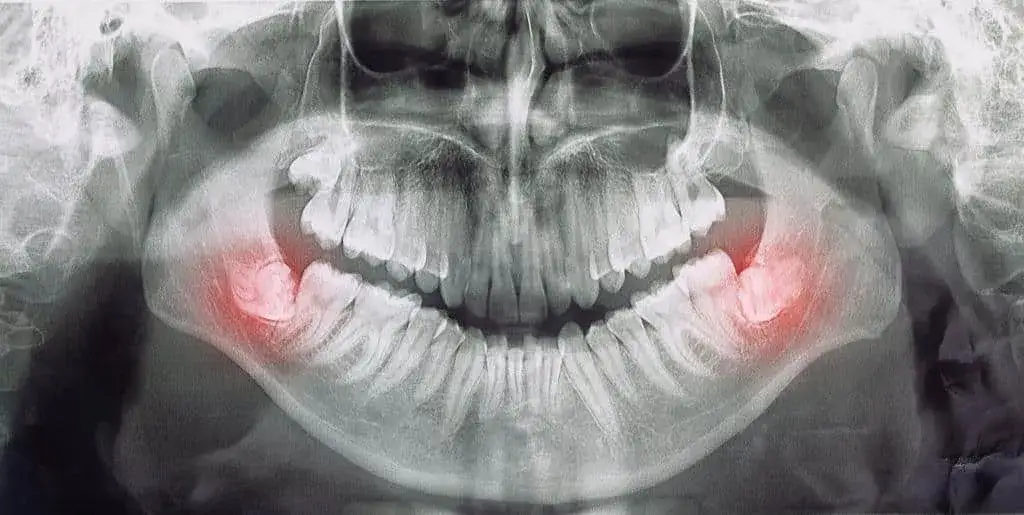

25 września 2025 Bóle Gdzie z bólem zęba Chełm? Znajdź natychmiastową pomoc dentystyczną Szukasz pomocy w przypadku bólu zęba w Chełmie? Sprawdź nasze rekomendacje klinik oferujących natychmiastową pomoc dentystyczną.